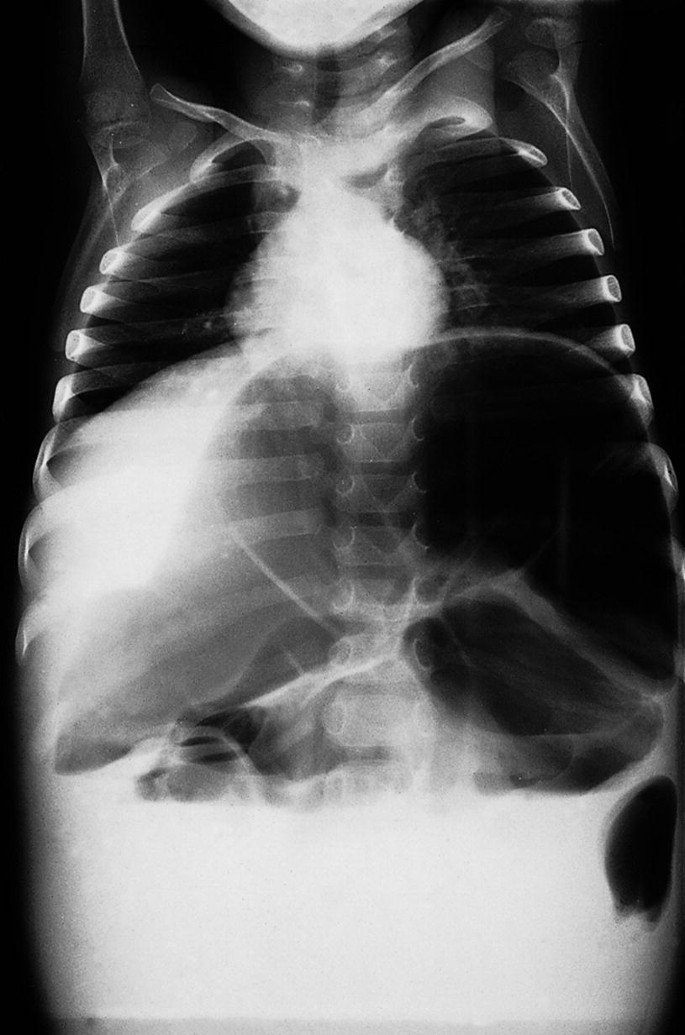

- Bildgebende Verfahren: Zur Beurteilung des Zustands des Dickdarms können auch bildgebende Verfahren wie Ultraschall, CT-Scans oder MRTs eingesetzt werden. Diese Verfahren liefern detaillierte Bilder des Dickdarms, die dem Arzt helfen können, Anomalien zu identifizieren.